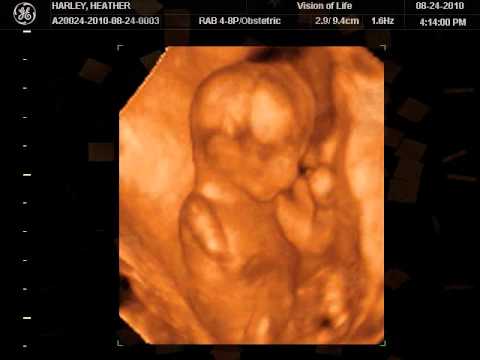

15 Weeks Ultrasound Pictures

Here are some ultrasound images at different times during second trimester.

Picture 3 is a 4D ultrasound of a fetus at 15 weeks pregnancy.